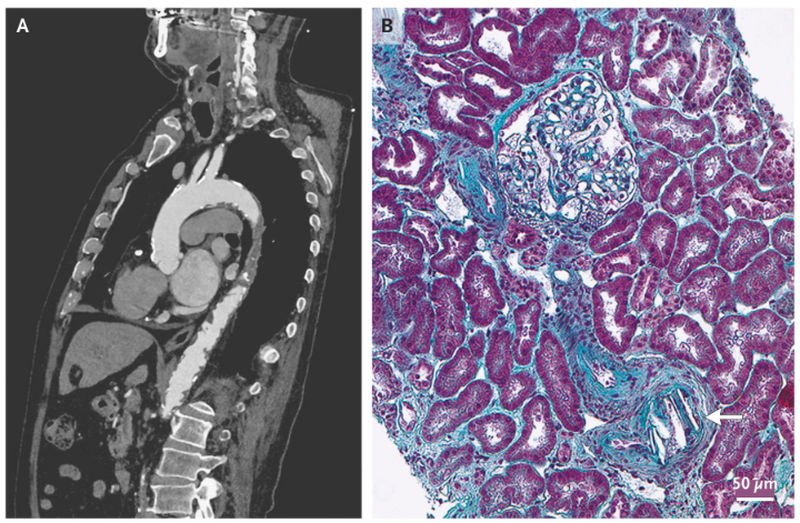

A 79-year-old man was admitted to the hospital after laboratory tests showed a serum creatinine level of 4.0 mg per deciliter (350 μmol per liter) (normal range, 0.7 to 1.2 mg per deciliter [60 to 100 μmol per liter]). He had no fevers, fatigue, weight loss, or myalgias. He had a history of ischemic cardiomyopathy and had chronic kidney disease (with a baseline serum creatinine level of 1.6 mg per deciliter [140 μmol per liter]), and he had undergone transcatheter aortic-valve replacement 1 month earlier. Physical examination showed cyanosis of both feet. Additional skin examination showed no livedo reticularis, and eye examination showed no Hollenhorst plaques. Additional laboratory tests showed a total white-cell count of 6800 per microliter with 15% eosinophils (absolute eosinophil count, 1050 per microliter; normal value, <500). Computed tomographic angiography that had been performed before transcatheter aortic-valve replacement showed diffuse atheroma in the aorta, with evidence of complex plaques (Panel A). Renal biopsy performed during the current admission revealed multiple needle-shaped clefts in arteries and glomeruli (Panel B, arrow), which confirmed cholesterol crystal embolization. The patient was treated with glucocorticoids and continued his previously prescribed treatment with aspirin and a statin. Hemodialysis was not initiated, and his renal function gradually improved. At a 6-month follow-up visit, the patient’s serum creatinine level was 2.2 mg per deciliter (190 μmol per liter).